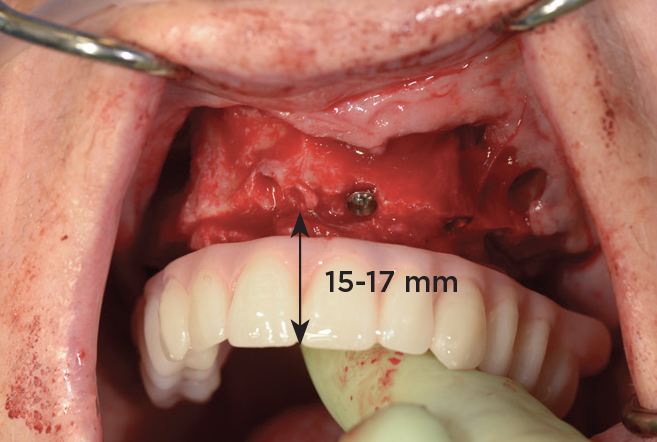

An important advantage of this approach is the ability to simulate bone reduction on the models and verify the presence of 15 mm to 17 mm and 13 mm to 15 mm of required inter-occlusal space for maxillary and mandibular restorations, respectively. This creates a platform for a diagnostic wax-up of the proposed dental rehabilitation and fabrication of wax prosthesis try-ins when necessary. Finally, a modified All-on-4 provisional prosthesis surgical and restorative guide developed by the authors for restoration-driven surgery and simplified restorative procedures is fabricated (Figure 2 through Figure 8).

Fig 4. Diagnostic wax-up performed after model surgery simulating maxillary tooth extraction. Note that inferior repositioning of the incisal plane helped create the 15 mm to 17 mm inter-occlusal space needed for the maxillary All-on-4 provisional restoration.

Figure 4